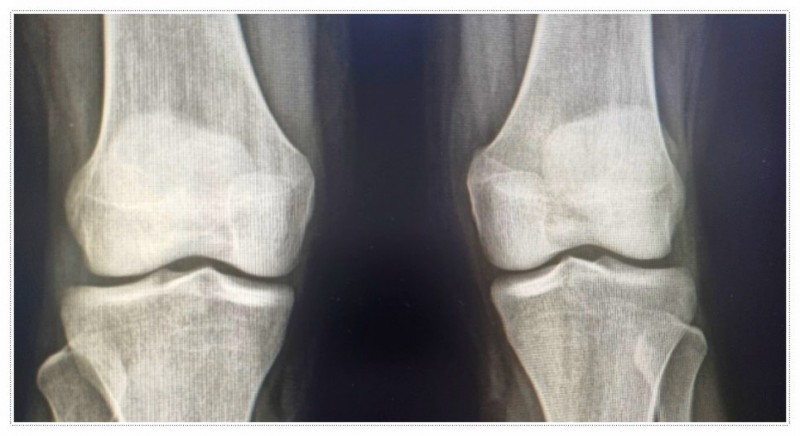

일반적으로는 X-ray 검사와 보행 분석 등을 통해 상태를 꼼꼼히 확인합니다.